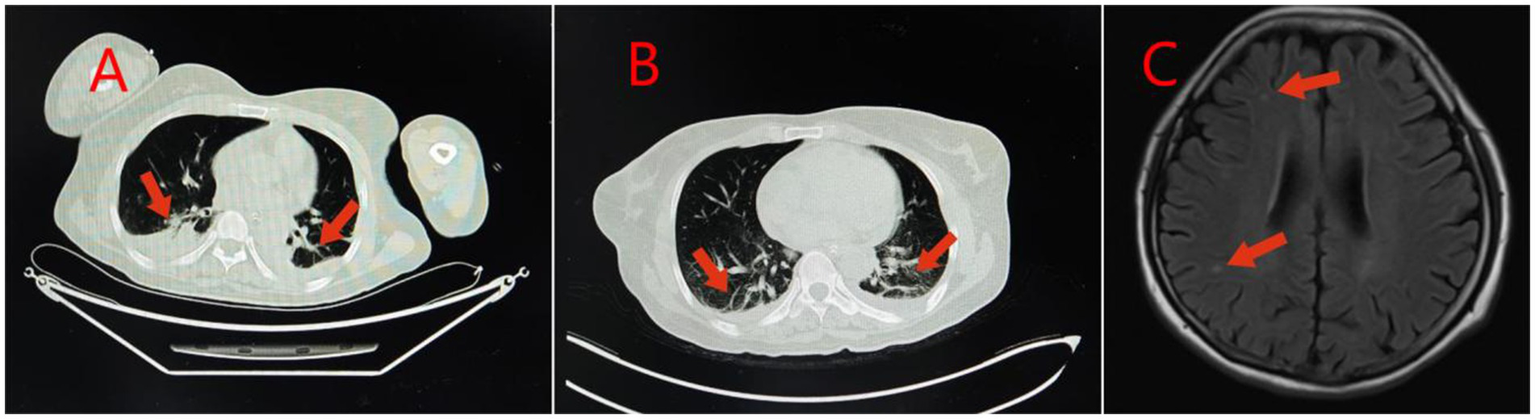

Figure 3

Imaging findings in Case 2: Panel (A) Lung CT shows inflammation or hypostatic changes in both lungs, and a small amount of pleural effusion in both pleural cavities; Panel (B) Reexamination of lung CT shows inflammation, fibrous foci, and hypostatic changes in both lungs, and a small amount of pleural effusion in both pleural cavities; Panel (C) Brain MRI shows a small amount of ischemic degenerative foci in the white matter of both cerebral hemispheres.

Case 2 was a 52-year-old woman with no previous health issues. She was admitted to the hospital on February 7, 2025, presenting with loss of consciousness and respiratory failure. Physical examination showed a temperature of 36.7 °C, heart rate of 79 beats/min, respiratory rate of 20 breaths/min, blood pressure of 130/81 mmHg, and SpO2 of 98%, revealed a state of drug-induced sedation and intubation, with coarse bilateral breath sounds and a few moist rales. Admission diagnosis: Acute poisoning; Asphyxiating gas poisoning. Laboratory and imaging results are shown in Tables 1, 2 and Figure 3. She was treated with a combination of propofol and dexmedetomidine for sedation; betamethasone and flucloxacillin to control pulmonary inflammation; danshen polyphenols for cardiovascular protection; and mecobalamin and vitamin B1 for nerve nutrition. Continuous electrocardiogram monitoring was maintained throughout her stay. During her hospitalization, her respiratory indicators remained stable, and she gradually weaned off the ventilator. On February 15, 2025, the tracheal intubation was successfully removed, and her spontaneous breathing was normal. However, she was unable to communicate with others and occasionally had convulsions, presenting with a decorticate syndrome. She was discharged on February 30, 2025, and returned to a local hospital for neurological rehabilitation. She was re-examined at our hospital on April 7, 2025, and no significant abnormalities were found in the biochemical tests. Follow-up by phone showed that she was still undergoing neurological rehabilitation treatment.